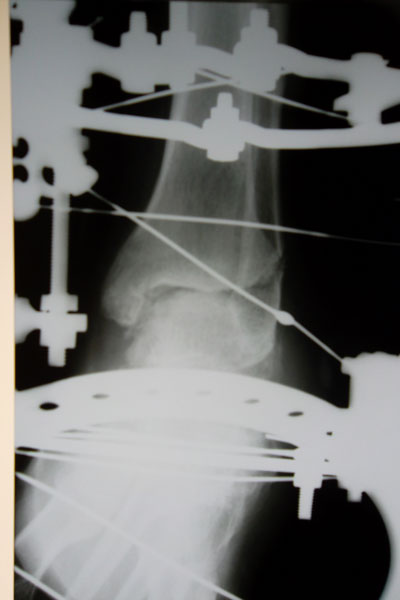

Рентген через 1,5 месяца после операцииХожу на костылях, перевязки за 150 км приезжаю делать в клинику один раз в 10 дней. Там же мне и делают компрессию по всем стержням. :)